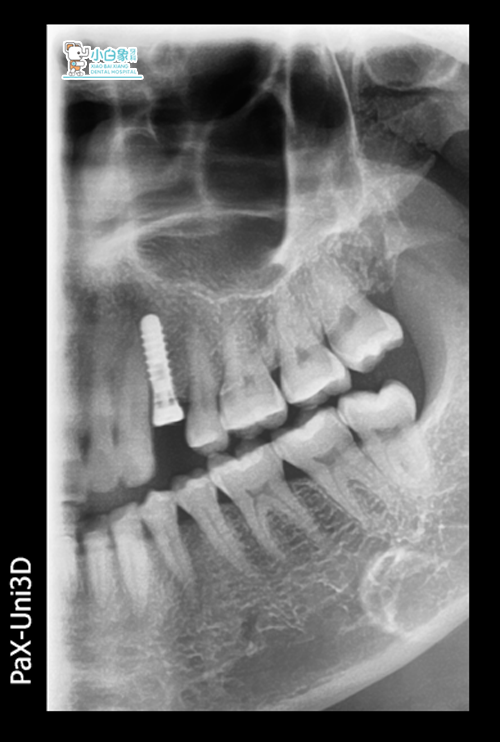

种植前设计:

CT测量骨量,骨高度16.5mm,骨宽度7.8mm,偏腭侧定点,选择创英4.1*12mm种植体一枚。

24局麻下拔除残根,偏腭侧定点,逐级预备种植窝洞,植入4.1*12mm,上愈合基台,严密缝合。

CT查患者根尖无炎症区域存在,颊侧骨壁较薄,腭侧骨量可,故在设计时考虑残根拔除同期种植这一方案,手术中偏腭侧定点备洞,初期稳定性达到15N以上,术后患者恢复较好。